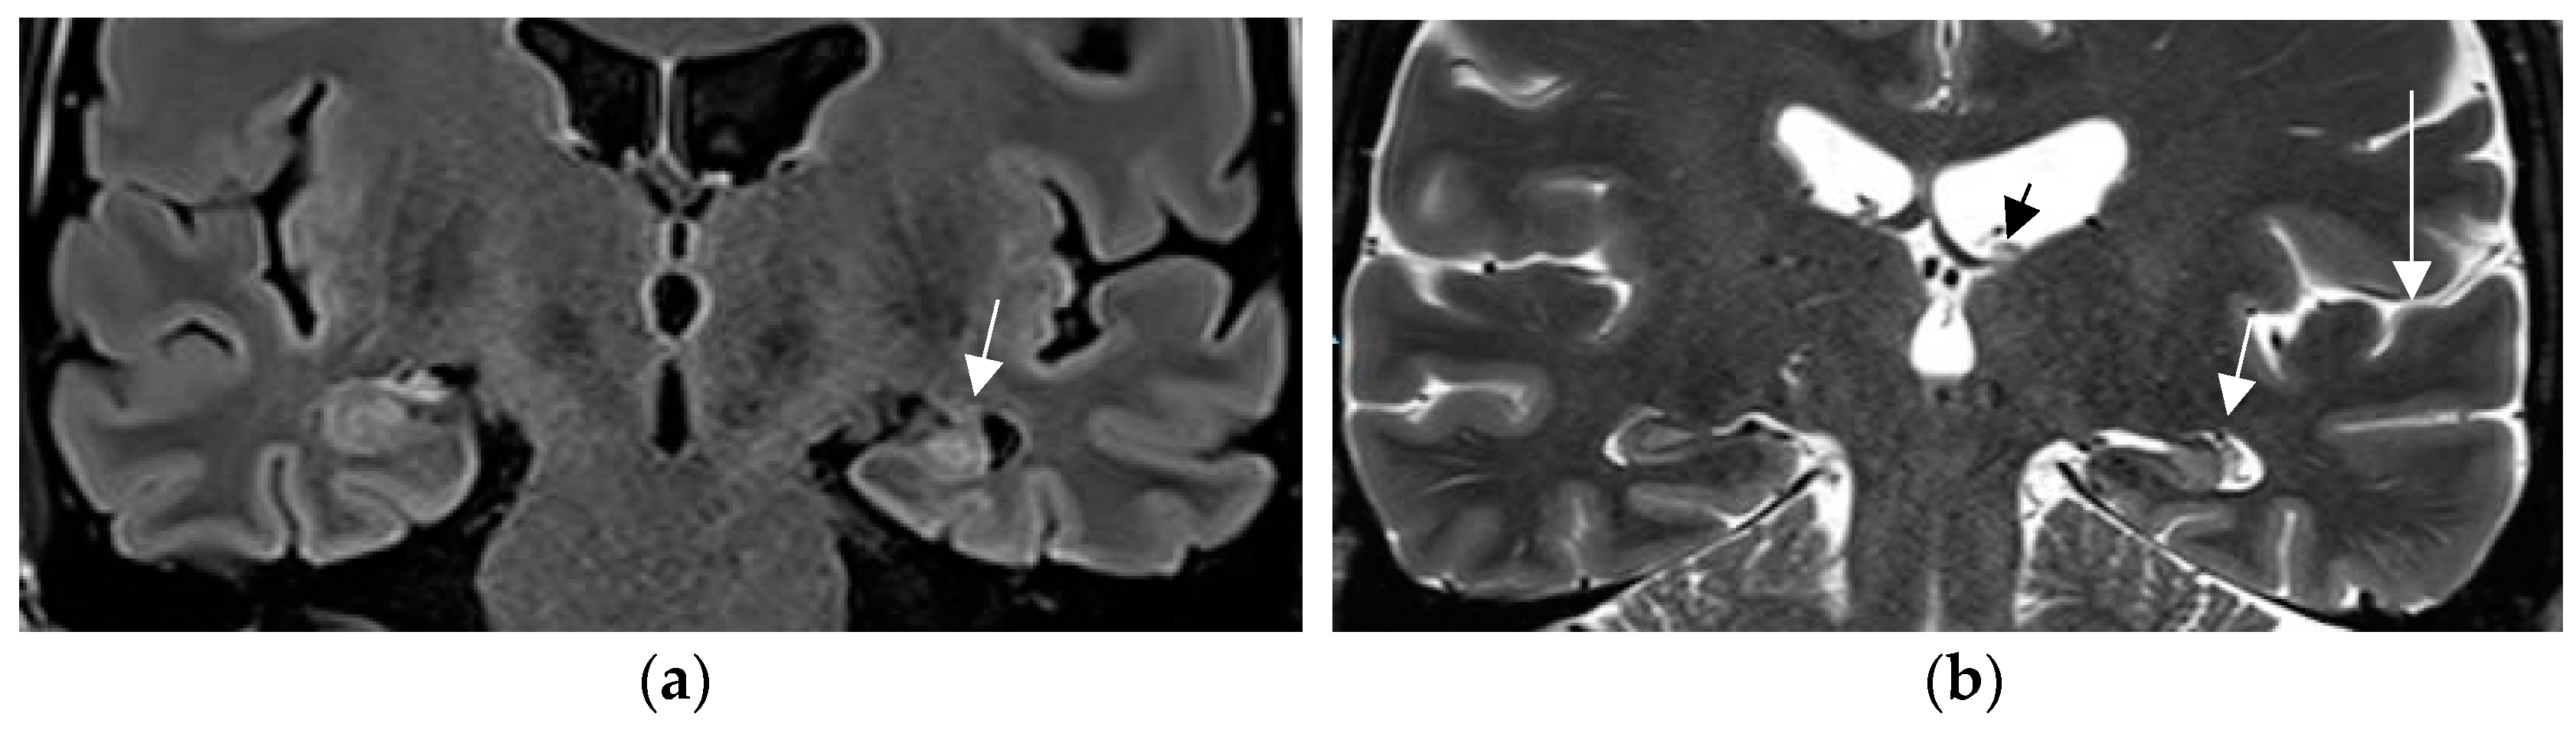

4.3. Expert Readers Take Advantage of the Added Value of an Epilepsy Specific Protocol

In a prior study [67] and in a recent prospective evaluation of the HARNESS protocol [68] in 123 and 131 patients, the sensitivity of MRI was particularly enhanced through interpretation by experienced readers for the diagnosis of hippocampal sclerosis and focal cortical dysplasia as the previously most frequently missed entities in adults and children, respectively. The combination of a dedicated MR and expert reader assessment increased detection of hippocampal sclerosis from 18 to 45% and of focal lesions from 50 to 91% [67]. Expert readers are more likely to recognize focal hippocampal sclerosis (Figure 2) and detect associated indirect signs such as atrophy of the ipsilateral fornix and mammillary body. Observations like the transmantle sign and subtle changes to adjacent white matter in focal cortical dysplasia and periventricular nodular and subcortical band heterotopia are challenging and less likely to be missed visually by an experienced reader.

Figure 2.

Hippocampal sclerosis depicted on coronal FLAIR (a) and T2 w sequence (white arrows) (b) (1.7 mm each) with volume reduction of the CA1-4 regions of the left hippocampus. FLAIR and T2 signal increases and slight atrophy of the left fornix (short arrow in (b)). Marked volume reduction of left temporal lobe as evidenced by the lower position of the left Silvian fissure (long arrow in (b)) compared to the right side.

A practical tip is to increase the spatial resolution in a 3T field magnet by lowering slice thickness from 3 mm to 2–1.5 mm for T2 sequences while maintaining signal intensity. This is enabled by application of a head coil with a high number of receive coils—e.g., 64 channels in a 3T field system (Figure 3). Sensitivity for lesion detection is thus increased from 53.1% to 85.9% [72]. The most common pathologies additionally encountered in this study were FCD, nonspecific gliosis, and oligodendrogliosis.

Figure 3.

Mild malformation of cortical development along left central sulcus hardly depicted by slight cortical blurring and subcortical gliotic foci on 1.7 mm coronal T2 w image (arrow in (a)) (a). Improved visualization of the mMCD on sagittal (b) and coronal (c) MP2RAGE sequence (0.9 mm) with slight nodular irregularity of both cortical borders and focal subcortical extension (c).